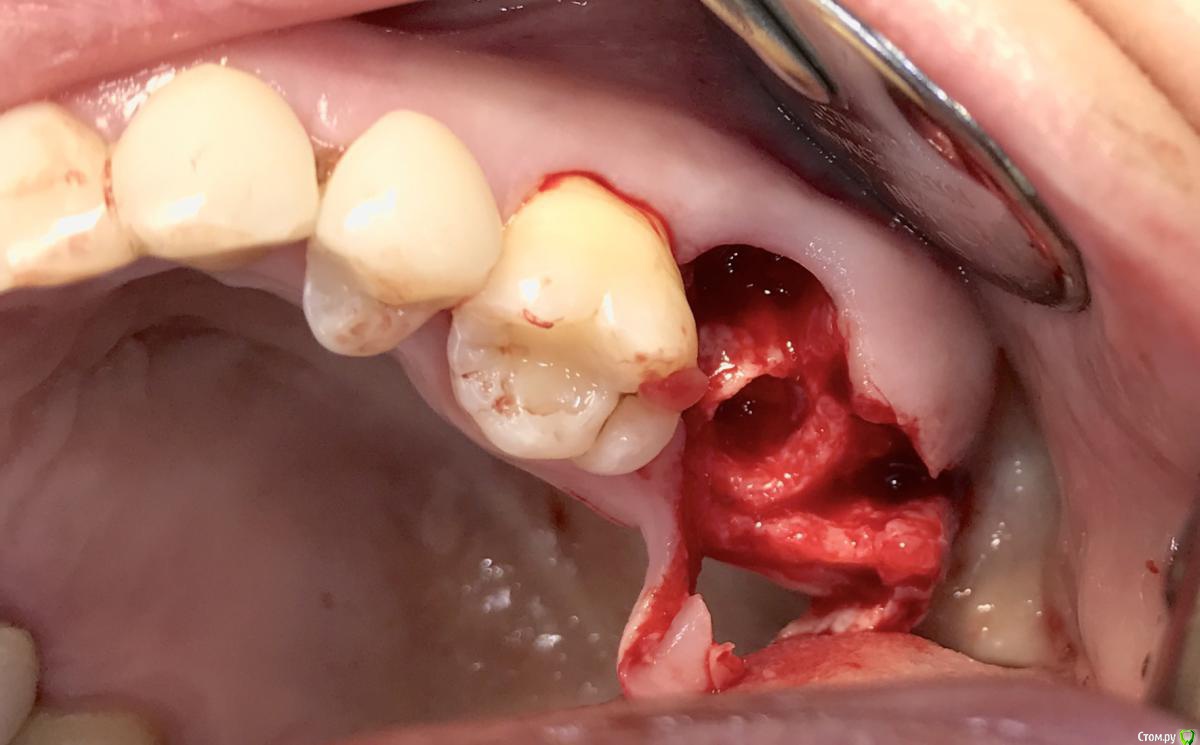

колесников Опубликовано 8 мая, 2017 Поделиться Опубликовано 8 мая, 2017 Немного модифицировал методику Палачи (образование прикреплённой кератинизированой десны междуимплантами,путём выделения и ротирования лоскута с неба). На в/ч у нас обширное поле деятельности со значительными полями кератинизированой слизистой на небе и бугре,что позволяет выделять полосочки не только для пластики в области имплантов,но и для консервации лунки. Можно выделить бугор на питательной ножке и перекинуть его на место 7го. Вариант отсутствует 6ой,присутствует 7ой - выделяем бугор и ведём по маргинальному краю неба у 7го расщепленным разрезом. Длинна может быть значительная,главное свободный конец зафиксировать не в стык а под расщеплённый лоскут принимающего ложа. Одним словом на в/ч с выделением просто. Как быть на н/ч? Обычно только свободный трансплантат с того же неба. Единственный вариант когда можно обойтись местными тканями:отсутствуют нижние 7,8,необходима консервация либо дополнительный объём кератинизированой десны у 7ки. Выделяется с дистального края лунки расщепленная кератинизрованая полоска и далее ведётся по язычному краю лунки . Получаем такую узкую ,но довольно длинную змейку,которую можем зафиксировать медиально, расположив по вестибулярному краю лунки ,либо по язычному ,либо завернуть спиралью. Можно ретромолярно выделить деэпителизированый трансплантат и на подобной змейке перенести его вестибулярно к 7ке. Фото неважные,изначально я не придал значения тому что делаю,позднее результат порадовал объёмом и скоростью регенерации. 1 Ссылка на комментарий

колесников Опубликовано 5 июля, 2019 Автор Поделиться Опубликовано 5 июля, 2019 Ещё раз о ретировалось лоскуте . Из ретромолярной зоны на н/ч перекинут Вестибулярно к 7ке и с неба перекинут Вестибулярно уже для верхней 7ки. Оба случая значительный дефект вестибулярной стенки,одномоментная имплантация,грануляции. Получается хороший стабильный и плотный каркас. 1 зона. 1 Ссылка на комментарий